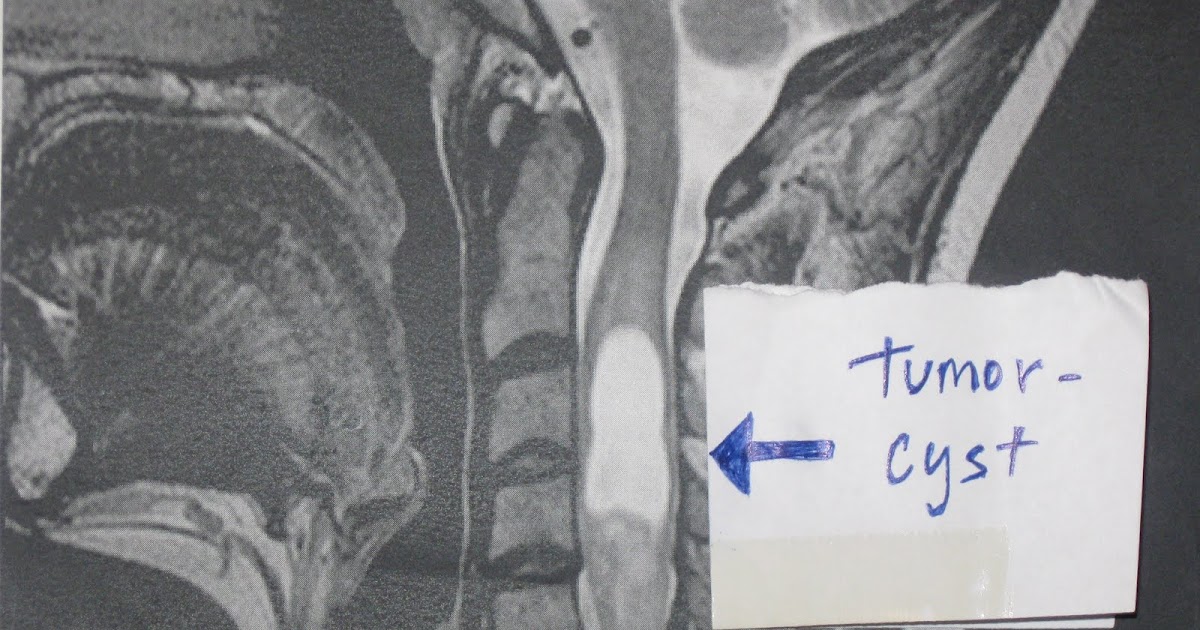

MRI of the cervical spine demonstrating erosive metastatic tumor of the Back Neck Tumor Symptoms Signs and symptoms may include: Learn the signs and symptoms of spinal tumors, such as back pain, muscle weakness, difficulty urinating, and paralysis. A vertebral tumor is a growth of cells in the bones of the spine that can be cancerous or not. Spinal tumors are abnormal growths in or around your spinal column. Pain at the site of the. Back Neck Tumor Symptoms.